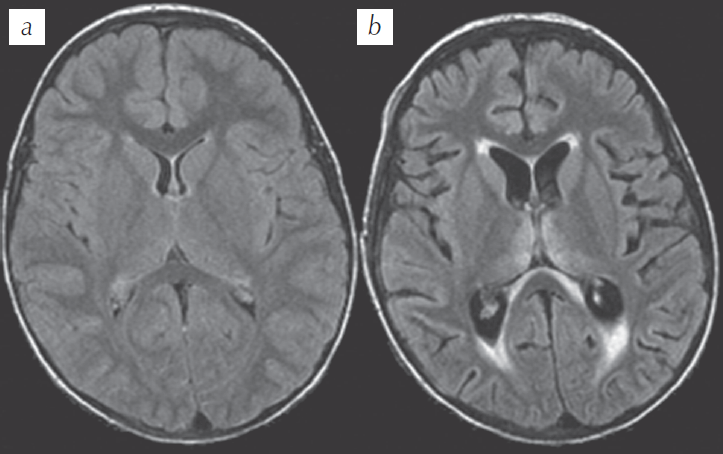

При проведении МРТ в остром периоде характерных воспалительных изменений в веществе мозга не выявляют (41 %) [3]. В 41 % случае регистрируют односторонние или двусторонние изменения сигнала на Т2 ВИ от гиппокампов, периинсулярных, лобно-париетальных областей, а также диффузные изменения по типу отека-набухания коры или таламусов. В единичных случаях диагностировали паренхиматозное кровоизлияние в мозжечок [20]. В хронической стадии FIERS у 50–65 % пациентов формируются атрофия и астроглиоз (мезиальный темпоральный склероз) как исход затяжной эпилептической энцефалопатии, что коррелирует с тяжестью и продолжительностью ЭС (рис. 1).

Рис. 1. Пациент, 4 года. Диагноз: FIRES: а — аксиальный срез, МРТ, Т1 ВИ на 1-й день госпитализации — без патологии; b — аксиальный срез, МРТ, Т1 ВИ на 30-й день госпитализации — нарастание атрофии, повышение сигнала от таламусов и перивентрикулярных отделов наружных отделов боковых желудочков (J Perumpillichira. 2014)

Fig. 1. Patient, 4 y. o. Diagnosis: FIRES: а — axial fluid attenuated inversion recovery image on day 1 of hospitalization shows no abnormalities; b — axial fluid attenuated inversion recovery image on day 30 of hospitalization — widening of sulci and lateral ventricles suggestive of diffuse cerebral atrophy, hyperintense signal changes are seen in bilateral thalami as well as along the ependymal margins of the ventricles and peri-atrial regions (J Perumpillichira. 2014)